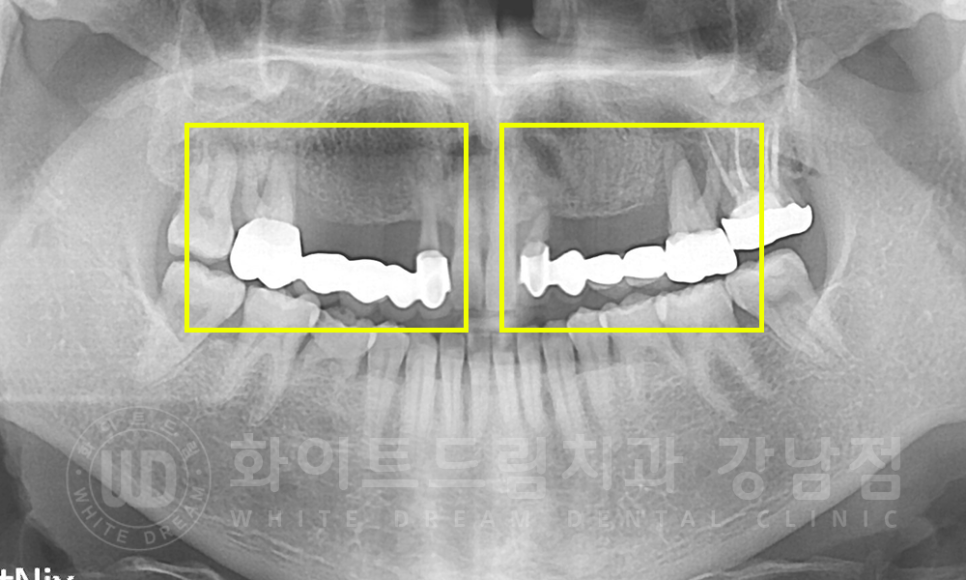

환자분의 x-ray 사진을 확인해 보겠습니다.

12 x 16번, 22 x 26번 치아가 각각 5unit 브릿지로 연결이 되어있습니다.

※ unit 앞에 숫자는 제작된 인공치 개수를 말합니다.

강남역 치과브릿지 / 치료 전 X-RAY